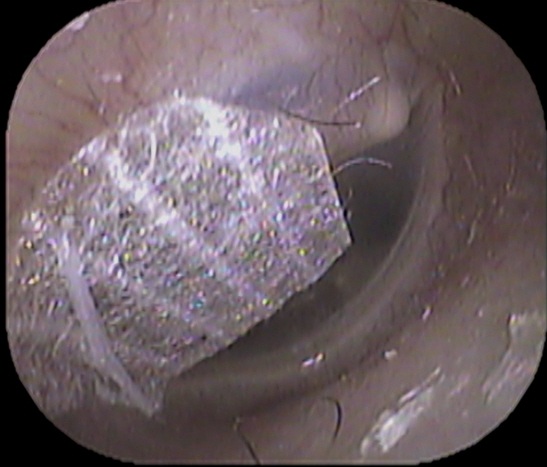

漢方薬で治療しましたが症状が続くため、鼓膜テープ治療をおこないました↓

鼓膜のテープ治療が効いたようで、症状は消失しました。